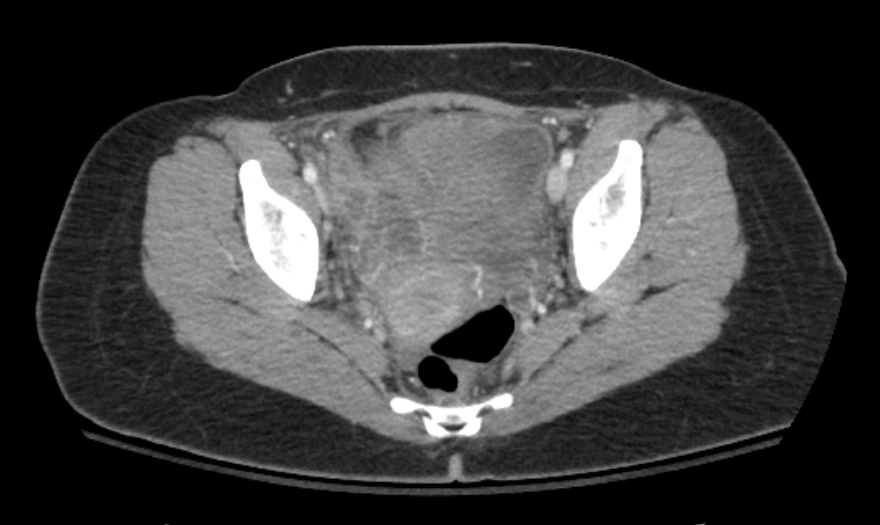

A 43 yo F presents to the ED with RLQ abdominal pain x 3 weeks. She reports 1 day of fever and chills. Abdominal/pelvic exam is significant for RLQ and suprapubic tenderness, as well as R adnexal tenderness and fullness. A CT scan is obtained. What's the diagnosis? (scroll down for answer)

Answer: Right tubo-ovarian abscess

- CT findings (as shown above) include tubular and cystic fluid collections with rim enhancement consistent with abscess formation